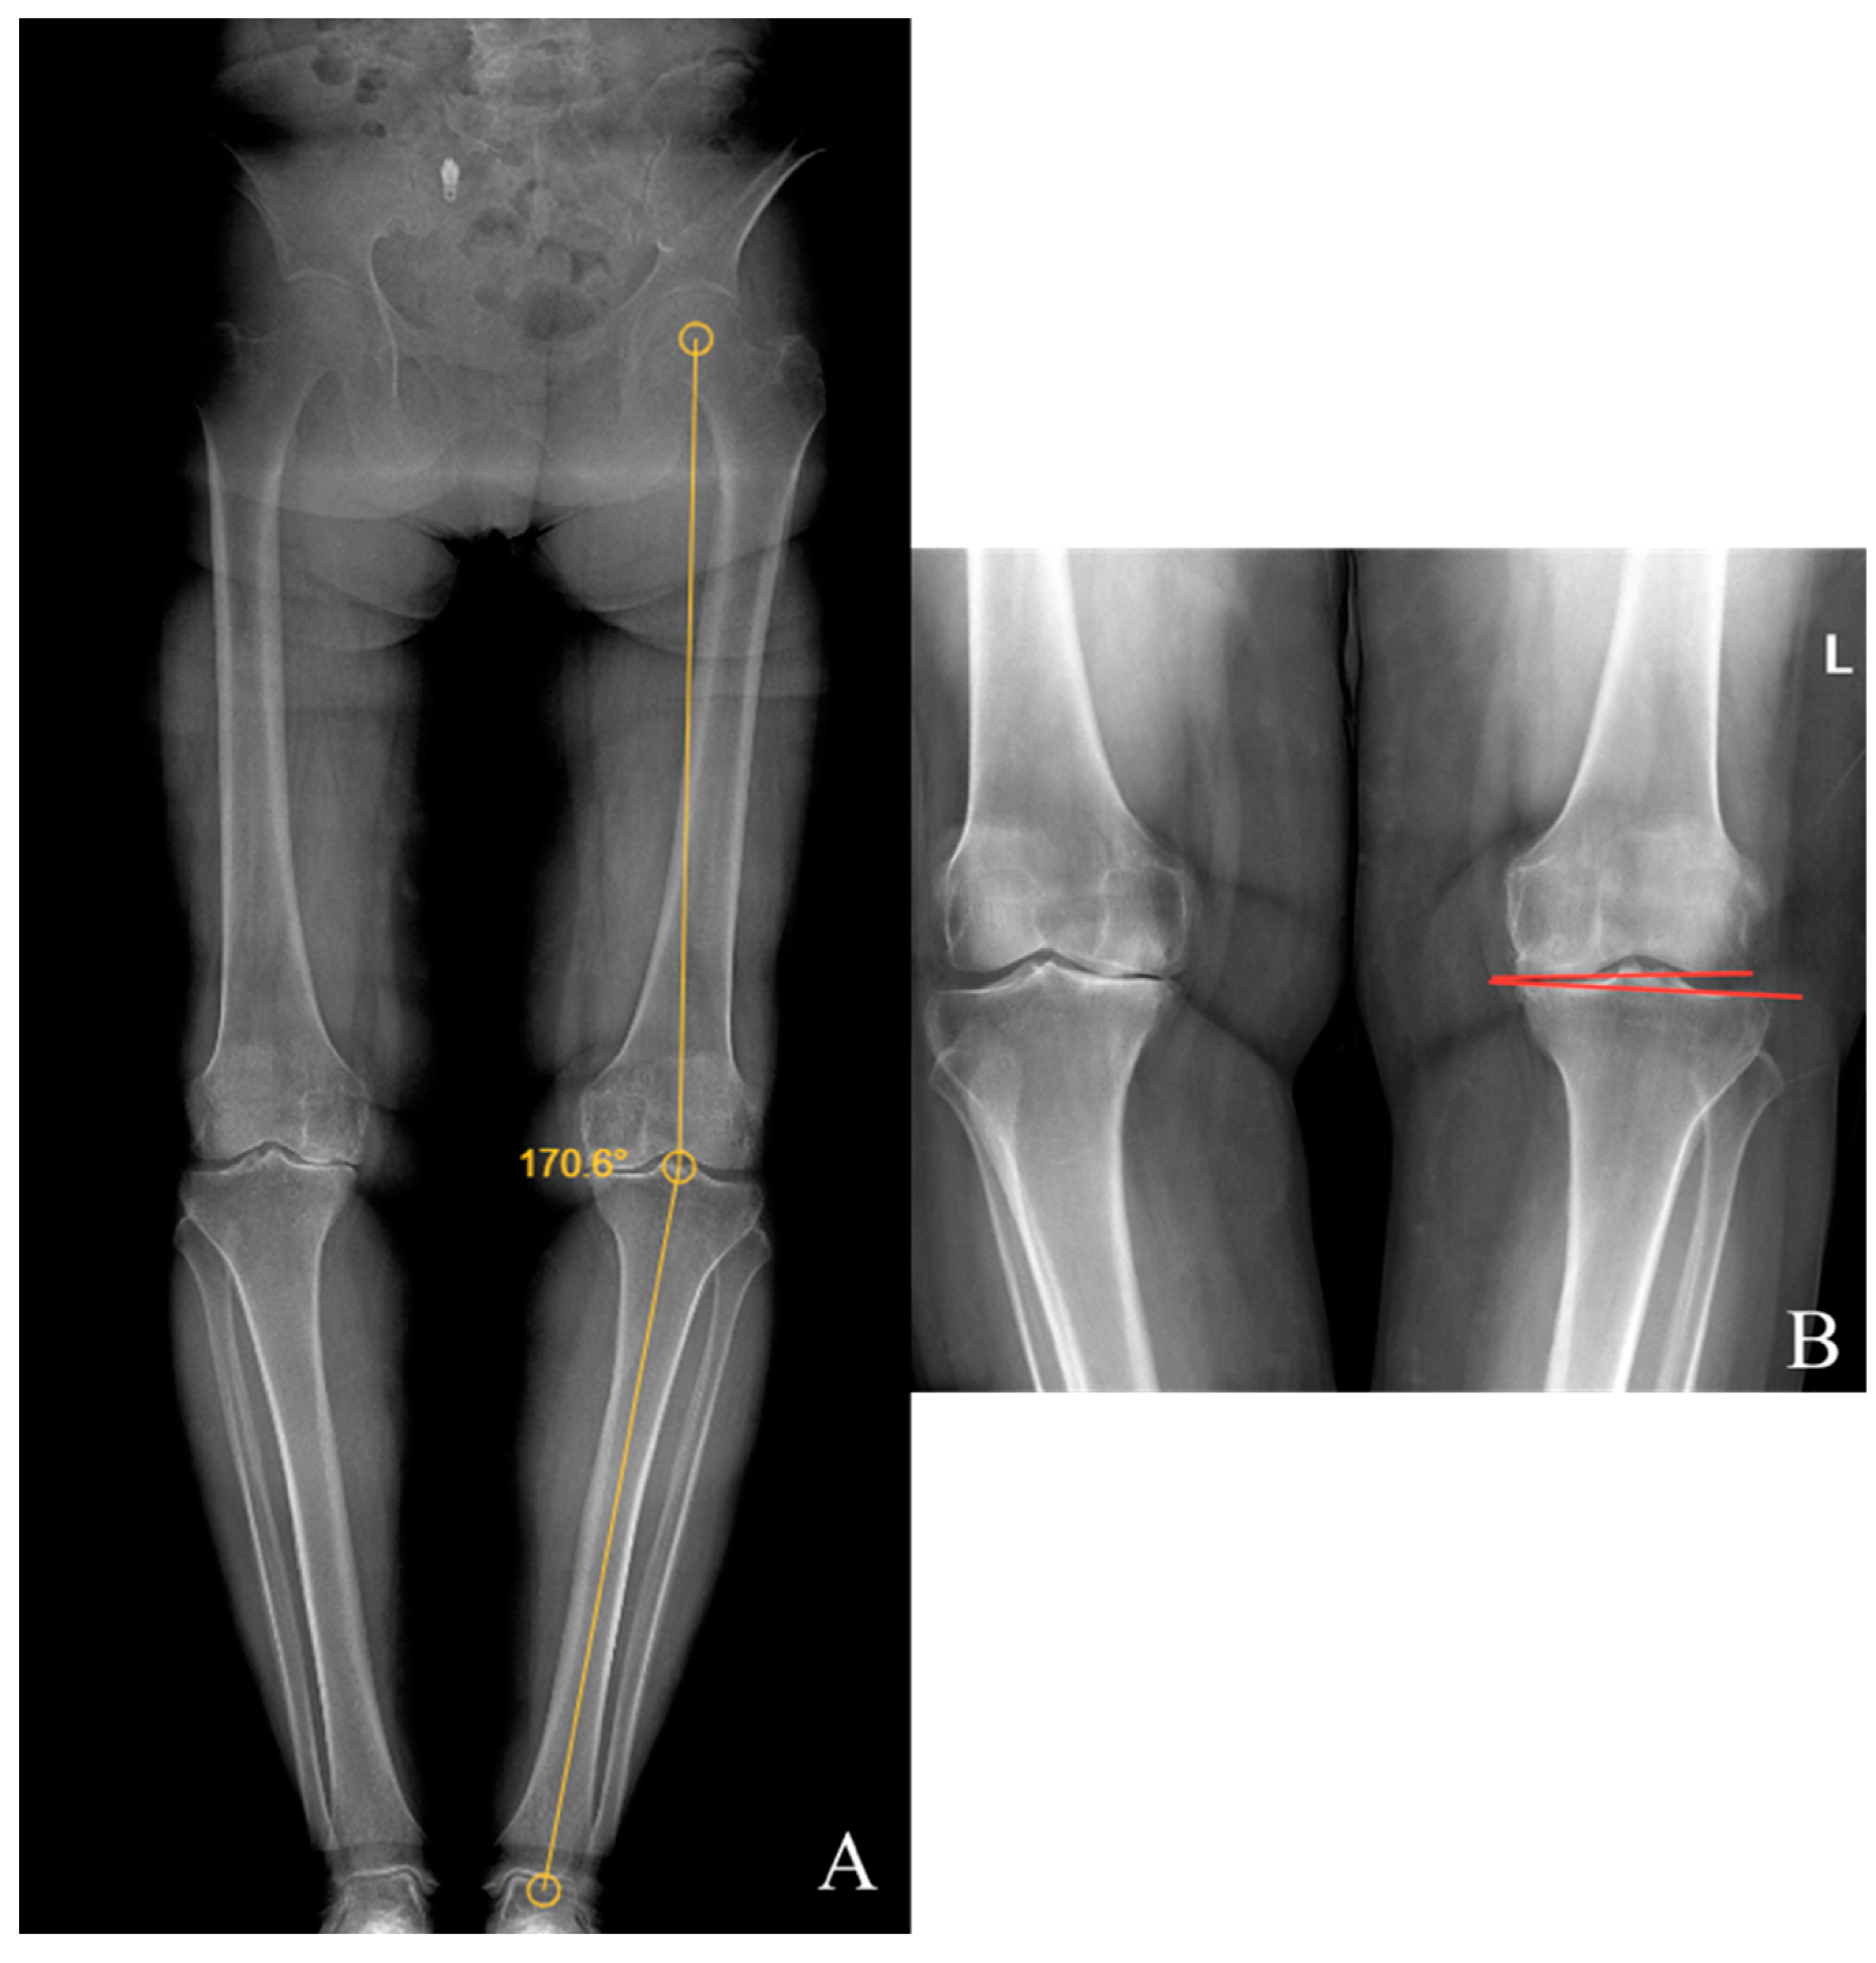

Preoperative and last visit full-leg standing radiographs were evaluated in each patient. Radiological measurements were performed using the picture archiving and communication system software. Two researchers independently measured the selected angles on all radiographs. The study utilized the average of the measured values. The hip–knee–ankle (HKA) angle was defined as the angle between a line drawn from the center of the femoral head to the femoral intercondylar notch and another line from the center of the tibial plateau to the mid-talar dome. The joint line convergence angle (JLCA) was measured as the angle between the femoral and tibial joint lines. The talar tilt (TT) angle was defined as the angle between the subchondral plate of the distal tibial articular surface and the talar dome, with the apex lateral angles positive and the apex medial angles negative. The ground talar dome (GT) angle was between the talar dome and a line parallel to the ground, and the ground plafond (GP) angle was between the subchondral plate of the distal tibial articular surface and a line parallel to the ground, both with apex lateral angles positive and apex medial angles negative.

The HKA, TT, JLCA, GT, and GP angles were measured on the patients’ radiographs (Figure 2 and Figure 3). The preoperative and last visit American Orthopaedic Foot & Ankle Society (AOFAS) scores were evaluated.

Figure 2.

(A) Hip–knee–ankle angle; (B) knee joint line convergence angle.